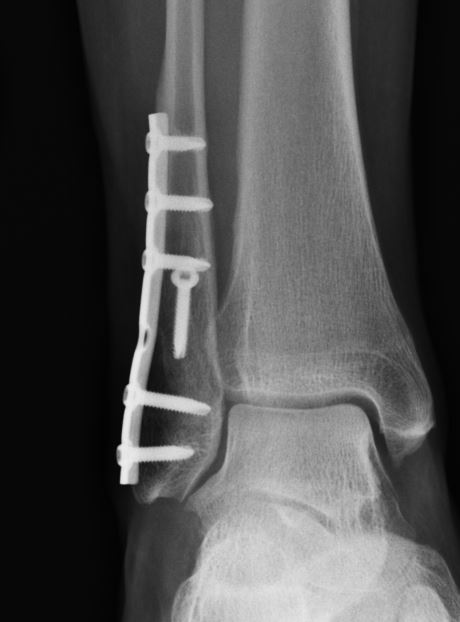

Home Schwerpunkte Krankheitsbilder Sprunggelenk-Fraktur Bruch oberes Sprunggelenk verheilt Weber B konsolidert Rötngen Zugschraube Bruch oberes Sprunggelenk verheilt Weber B konsolidert Rötngen Zugschraube Bruch oberes Sprunggelenk verheilt Weber B konsolidert Rötngen Zugschraube